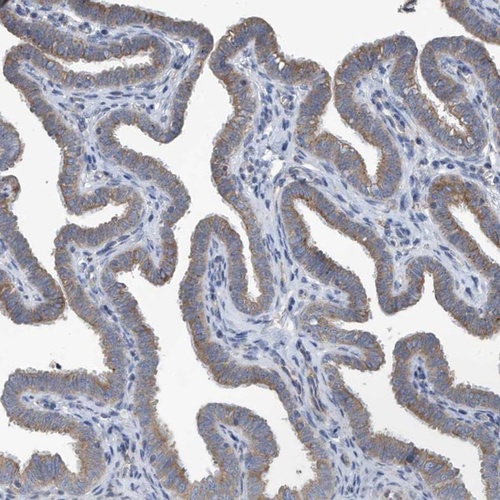

Immunohistochemical staining of human fallopian tube shows cytoplasmic positivity in glandular cells.